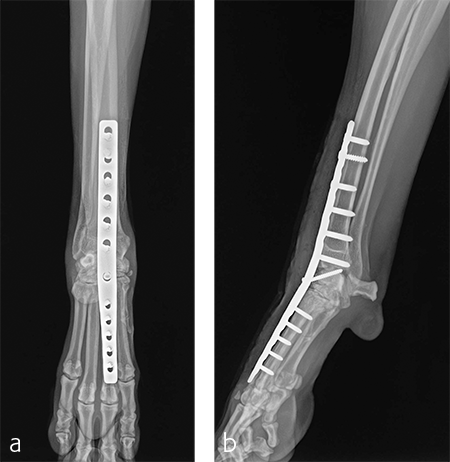

A 2.7/3.5 Pancarpal Arthrodesis was applied to the dorsal aspect of the carpus using a combination of locking and cortical screws. A 2.7 mm cortical screw was used to attach the plate to the radiocarpal bone. Five 2.7 mm locking screws were used to attach the plate to the 3rd metacarpal bone. Five 3.5 mm locking screws and one 3.5 mm cortical screw were used to attach the plate to the dorsal surface of the radius. A combination of locking and cortical screws was used to provide compression (cortical screw placed in eccentric position to provide compression across the radiocarpal joint) and achieve excellent stability and limb alignment. The incision was closed in routine fashion.

Postoperative radiographs revealed proper joint orientation and compression of the multiple antebrachiocarpal joint levels (Fig 5). Implant placement was considered excellent.

Treatment with a splint for several weeks resulted in no improvement. A pancarpal arthrodesis was performed with the 2.7/3.5 Pancarpal Arthrodesis Plate and a combination of standard cortical and locking screw fixation. An autogenous cancellous bone graft was collected from the left proximal humerus and placed at all joint levels.

Immediate postoperative images confirmed anatomic alignment and adequate carpal extension (Fig 10). At the 11-week postoperative follow-up examination, functional recovery was very good with images revealing stable implants and healing of the arthrodesis (Fig 11). The dog was then allowed to return to normal activity.